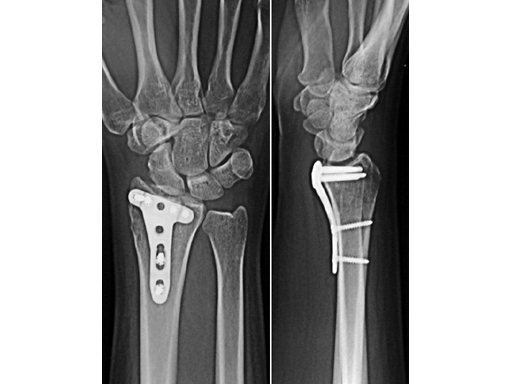

Case 1

Reversed Barton fracture 23-B3 in a 34-year-old woman after fall on outstretched hand.